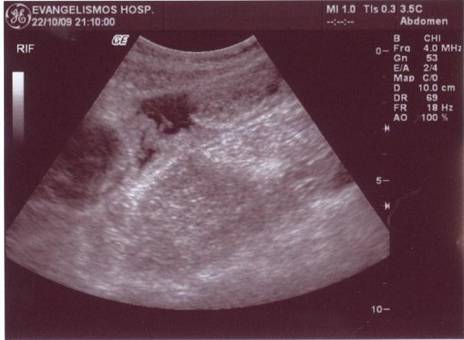

A 30-year old man presented with symptoms and signs of acute appendicitis. Abdominal imaging via ultrasound and computed tomography detected a mass in the right iliac fossa. Exploratory laparotomy revealed an appendiceal mass and gelatinous peritoneal fluid, while histopathology confirmed the diagnosis of pseudomyxoma peritonei arising from a mucocele of the appendix and attributed to an appendiceal cystadenocarcinoma. The clinical and imaging findings of this rare case are herein presented.